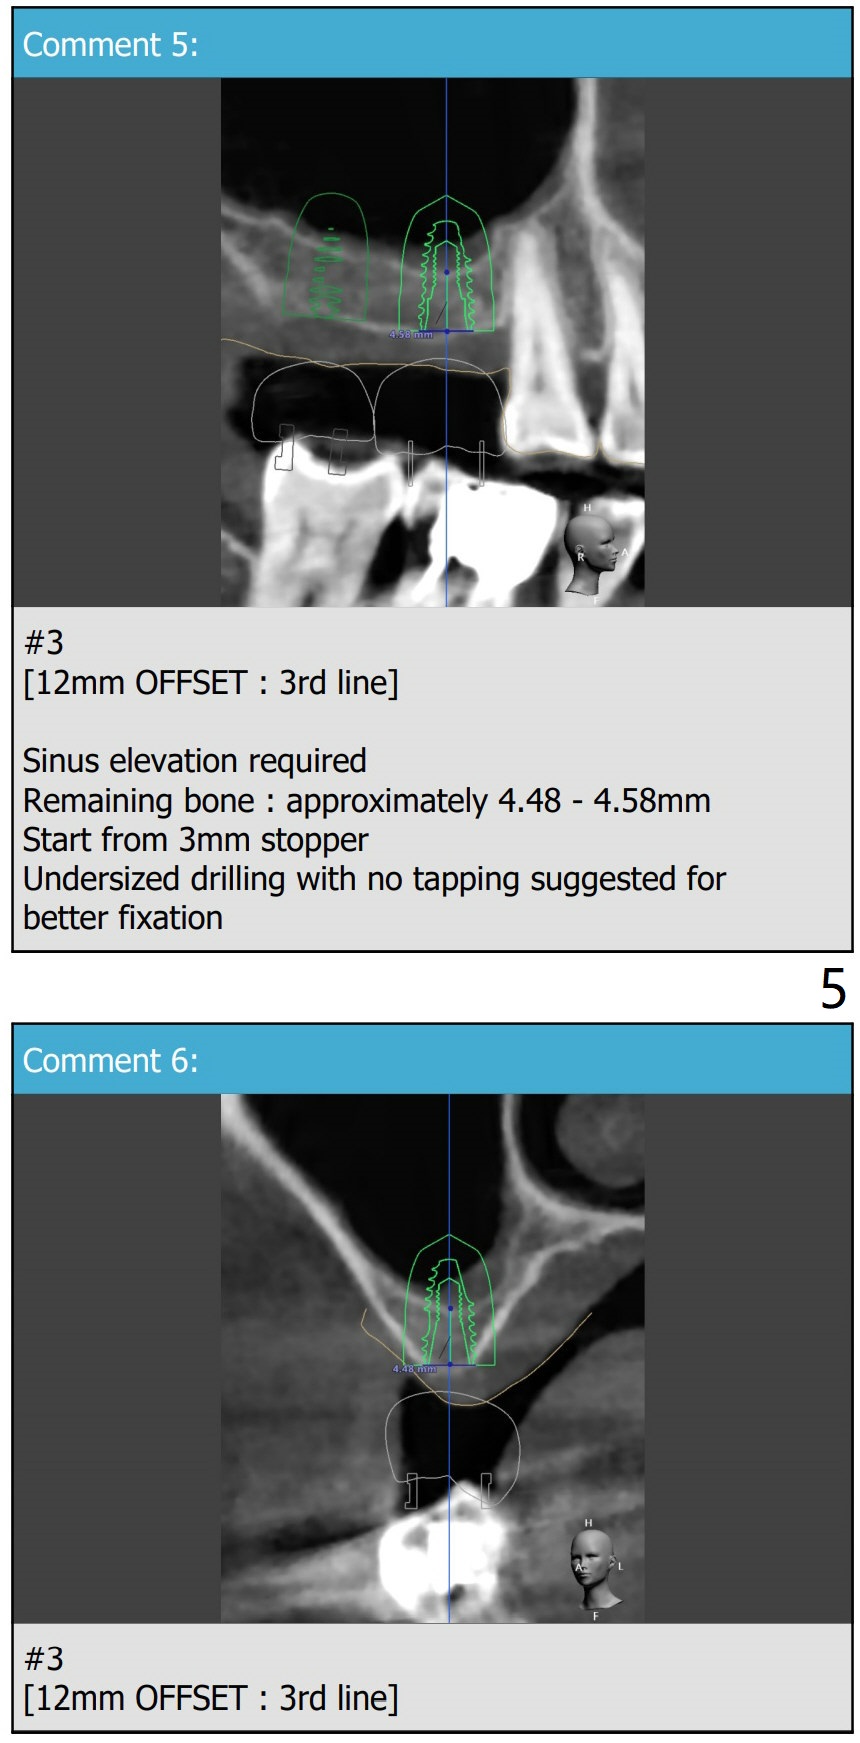

Narrow Implants with Lift